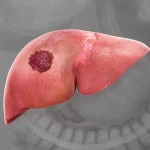

سرطان کبد بدخیم یکی از جدیترین بیماریهای دستگاه گوارش است که در سالهای اخیر شیوع بیشتری پیدا کرده است. این سرطان، زمانی اتفاق میافتد که سلولهای طبیعی کبد دچار تغییرات غیر قابل کنترل میشوند و شروع به رشد سریع و بی رویه میکنند. نتیجهی این تغییرات، تشکیل تومورهایی است که عملکرد حیاتی کبد را مختل میکنند. در این مقاله، به بررسی همه جانبه این بیماری، علل، علائم، روشهای تشخیص و درمانهای نوین آن میپردازیم همچنین شما میتوانید سوالات خود را به صورت مستقیم از متخصص بپرسید.

سرطان کبد بدخیم چه تفاوتی با تومور خوشخیم دارد؟

کبد میتواند دچار دو نوع تومور شود: تومور خوشخیم و تومور بدخیم. تومورهای خوشخیم معمولا رشد آهستهای دارند و به سایر بافتها سرایت نمیکنند. اما تومور بدخیم کبد یا همان سرطان کبد بدخیم، رشد تهاجمی دارد و ممکن است به سایر اندامها گسترش یابد. از آنجایی که علائم سرطان کبد معمولا خاموش و بسیار نامحسوس است و بیمار علائم آن را بیماریهای ساده تر اشتباه میگیرد و پیگیری نمیکند، این سرطان دیر و در مرحله بدخیم تشخیص داده میشود.